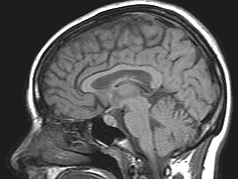

Brain MRI Regression Predicting the age of an individual based on brain MRI features. Fair Auction Design Improving the fairness between participants in a simulated ad auction.